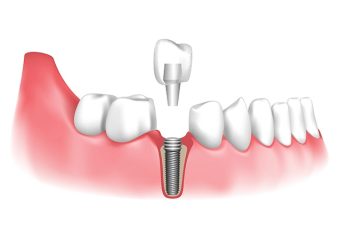

- ایمپلنت دندان اصفهان

پری ایمپلنتیت، بهعنوان یکی از چالشهای مهم در حوزه ایمپلنتولوژی، به التهاب و عفونت بافتهای اطراف ایمپلنتهای دندانی اشاره دارد که در صورت عدم درمان مناسب، میتواند به از دست رفتن ایمپلنت منجر شود. در سالهای اخیر، روشهای نوینی برای مدیریت و درمان این عارضه معرفی شدهاند که در ادامه این مقاله سایت دکتر ندا مکانیک بهترین ایمپلنت اصفهان به بررسی آنها میپردازیم.

استفاده از لیزر در درمان پری ایمپلنتیت

لیزرهای دندانپزشکی به دلیل توانایی در حذف بافتهای عفونی و ضدعفونی کردن نواحی مبتلا، بدون آسیب به بافتهای سالم، مورد توجه قرار گرفتهاند. این روش با کاهش عمق پاکتهای پری ایمپلنت و بهبود اتصال بافتهای نرم به سطح ایمپلنت، به بهبود وضعیت بیمار کمک میکند.

آنتیبیوتیکهای موضعی

استفاده از آنتیبیوتیکهای موضعی بهعنوان مکملی برای دبریدمان مکانیکی، میتواند به کاهش بار باکتریایی و التهاب کمک کند. مطالعات نشان دادهاند که ترکیب دبریدمان دستی با آنتیبیوتیکهای موضعی میتواند به بهبود عمق پروبینگ و کاهش خونریزی منجر شود.

تکنیکهای جراحی بازسازی استخوان

در موارد پیشرفته پری ایمپلنتیت که تخریب استخوانی قابلتوجه است، استفاده از تکنیکهای جراحی بازسازی استخوان ضروری میشود. این روشها شامل پیوند استخوان اتوژن، استفاده از مواد جایگزین استخوانی مانند زنوگرفتها و آلوگرفتها، و تکنیکهای هدایتشده بازسازی بافت (GBR) میباشند. هدف از این مداخلات، بازگرداندن حجم و تراکم استخوان از دست رفته و فراهم کردن بستر مناسب برای پایداری ایمپلنت است.

تکنیکهای نوین در بازسازی استخوان

علاوه بر روشهای سنتی، تکنیکهای نوینی مانند کشش کال استخوانی (Distraction Osteogenesis) و استفاده از سلولهای بنیادی برای بازسازی استخوان معرفی شدهاند. کشش کال استخوانی با ایجاد فاصله در استخوان و تحریک رشد استخوان جدید، به افزایش عرض و ارتفاع استخوان کمک میکند. همچنین، استفاده از سلولهای بنیادی مشتق از دندان یا مغز استخوان، بهعنوان رویکردی نوین در مهندسی بافت، پتانسیل بالایی در بازسازی استخوانهای فک نشان داده است.

پیشگیری و مدیریت بالینی

پیشگیری از پری ایمپلنتیت با رعایت بهداشت دهان و دندان، مراجعات منظم به دندانپزشک و انجام تمیزکاریهای حرفهای امکانپذیر است. در صورت بروز علائم اولیه مانند خونریزی، تورم یا درد در ناحیه اطراف ایمپلنت، مراجعه فوری به دندانپزشک برای ارزیابی و شروع درمان ضروری است. مدیریت بالینی این عارضه باید بر اساس شدت بیماری، میزان تخریب استخوانی و شرایط کلی بیمار تنظیم شود.

نتیجهگیری

پری ایمپلنتیت بهعنوان یک چالش جدی در حوزه ایمپلنتهای دندانی، نیازمند تشخیص بهموقع و استفاده از روشهای درمانی مؤثر است. ترکیب روشهای نوین مانند استفاده از لیزر، آنتیبیوتیکهای موضعی و تکنیکهای جراحی بازسازی استخوان، میتواند به بهبود نتایج درمانی و افزایش طول عمر ایمپلنتها کمک کند. همچنین، تحقیقات در زمینه استفاده از سلولهای بنیادی و تکنیکهای مهندسی بافت، افقهای جدیدی را در درمان و بازسازی بافتهای از دست رفته نشان میدهد.